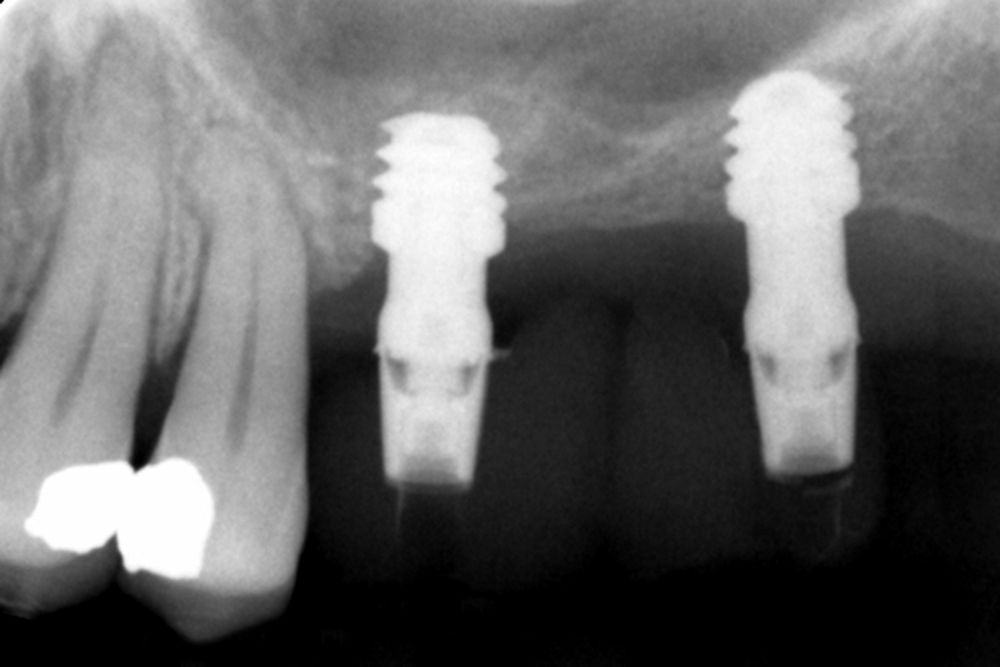

All implants were rehabilitated in two phases and all of them were ferulized to other implants in the rehabilitation. In all cases, screwed prostheses of more than one implant with intermediate elements (transepithelial) were performed, ferulizing to other implants with a length of 4.5 or 5.5 mm. In all situations, a progressive prosthesis load was carried out 6 months after insertion of the implant consisting of a provisional structure finished in resin to move to a definitive metal-ceramic prosthesis. In all cases, the initial transepithelial are preserved to maintain the hermeticity achieved in the first phase of prosthesis manufacture.

No implants failed in the follow-up period and no biological complications were found in the surgery. The postoperative condition of all patients was excellent with minimal discomfort in the surgery area and with minimal postoperative inflammation.

Figures 2-19 show one of the cases included in the study.